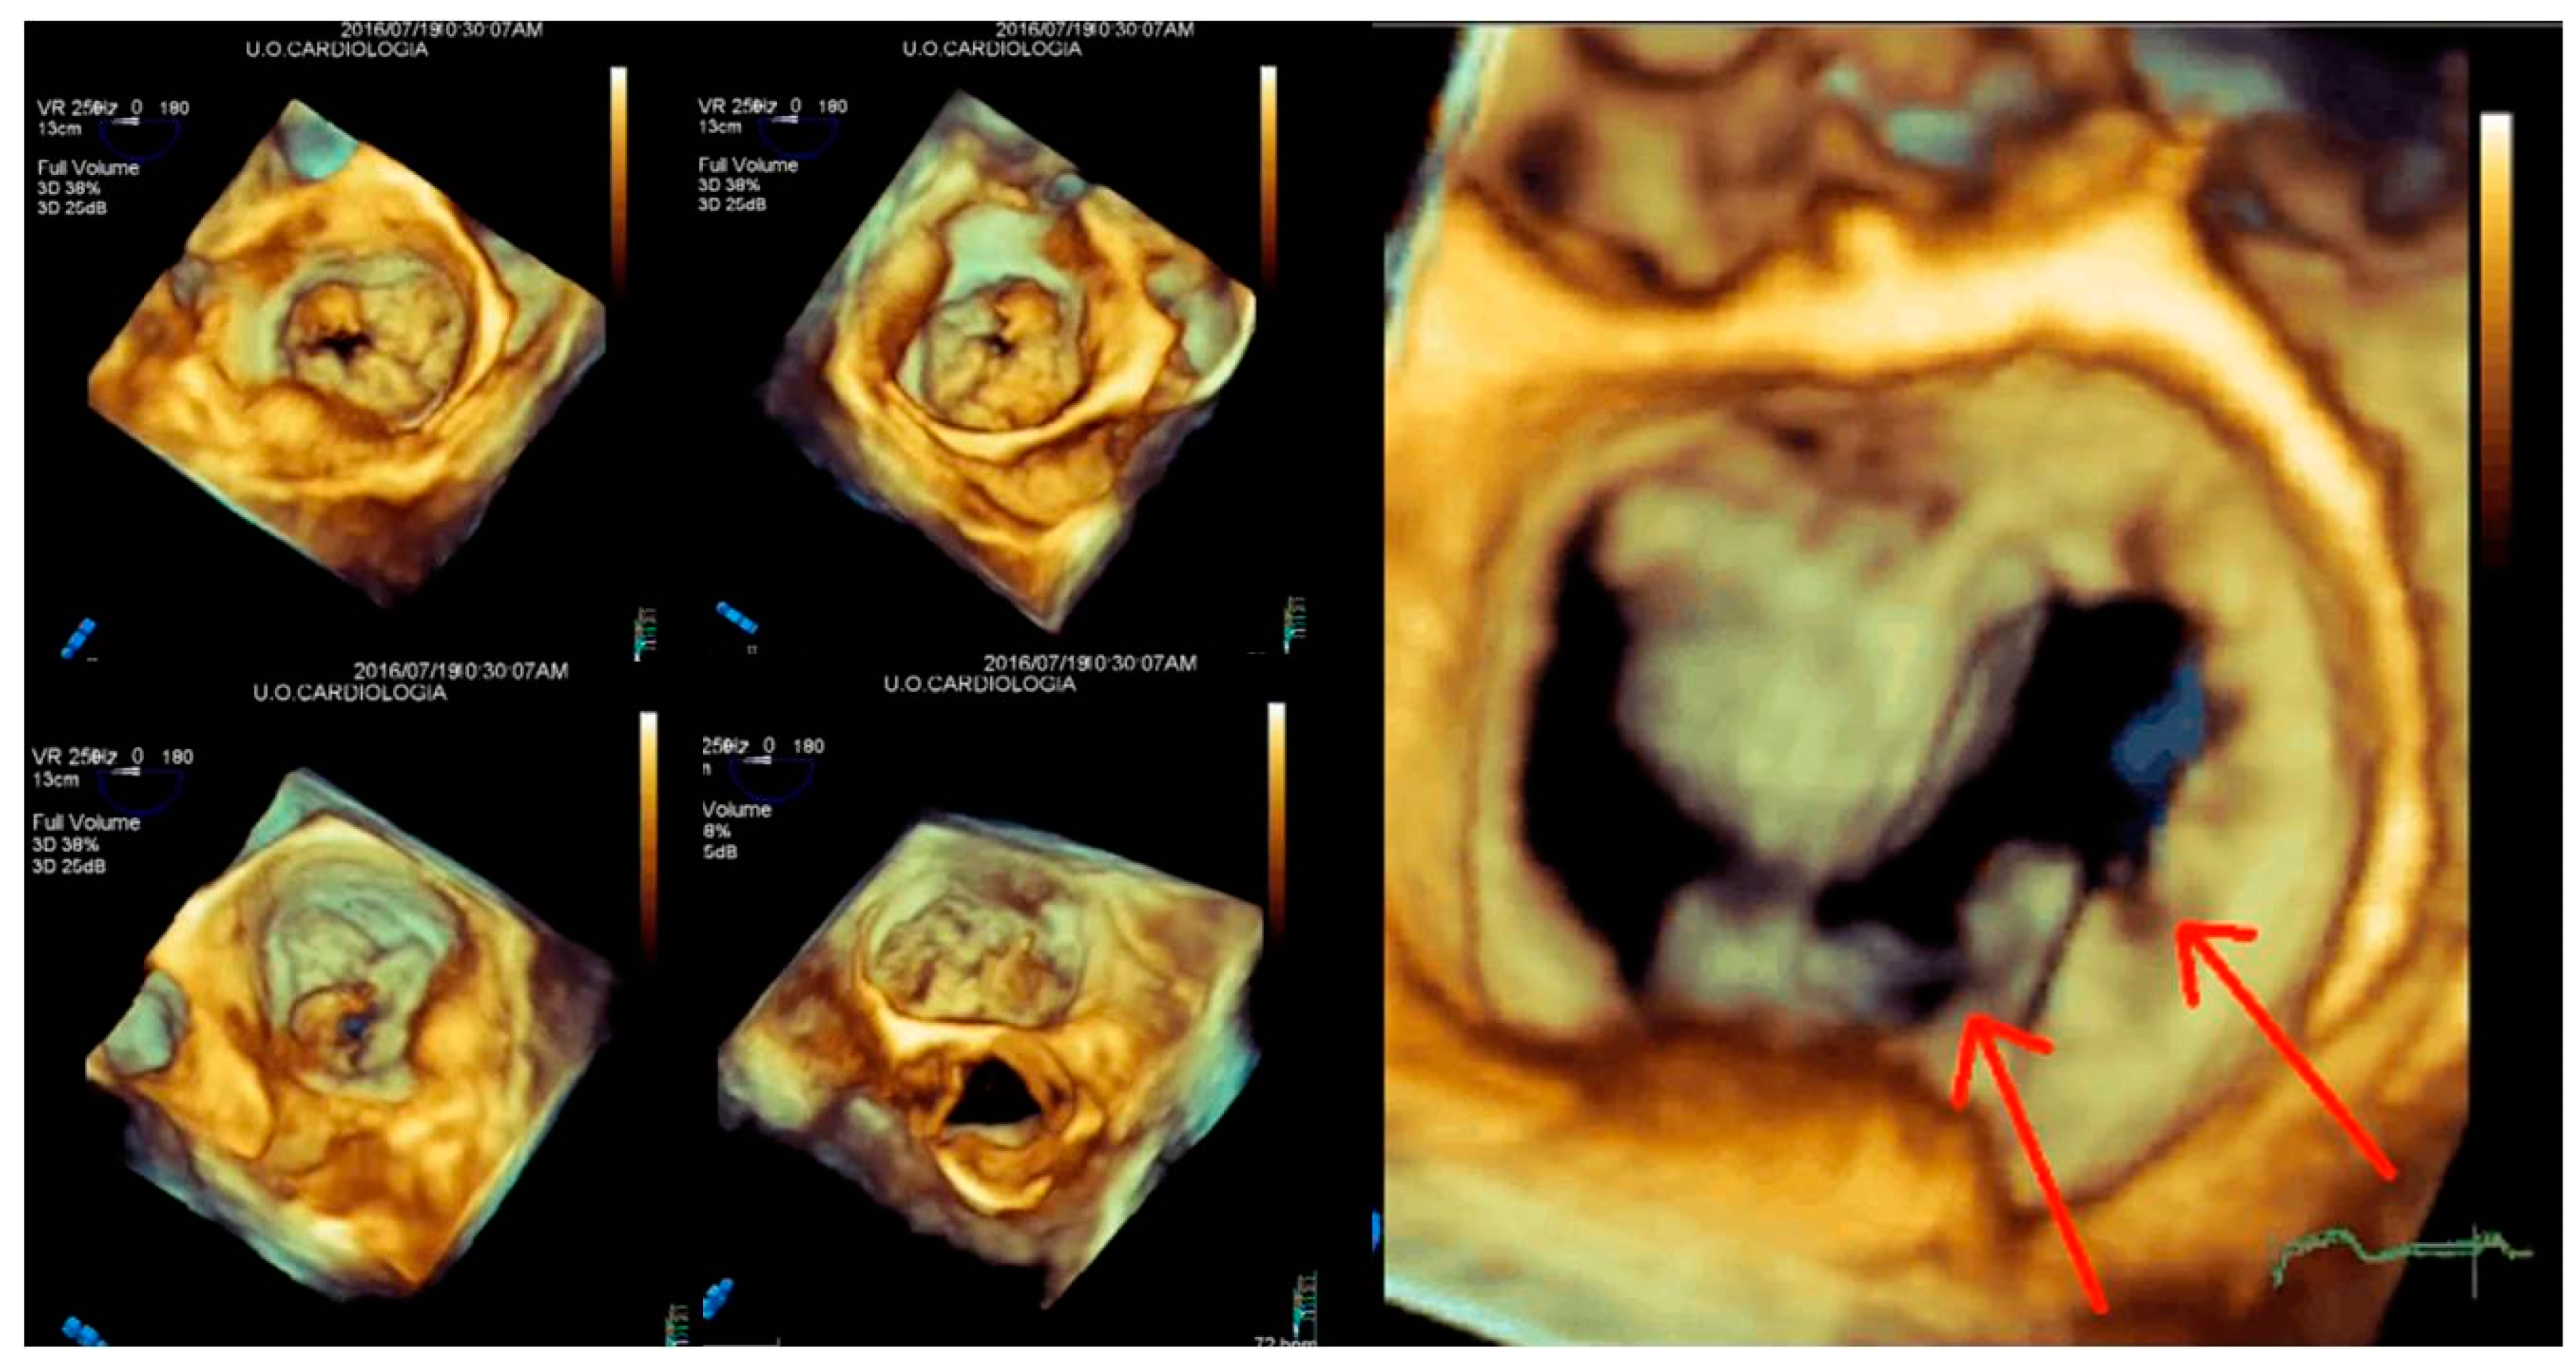

4.3. Mitral Valve Repair Procedures

4.4. Surgical Repair